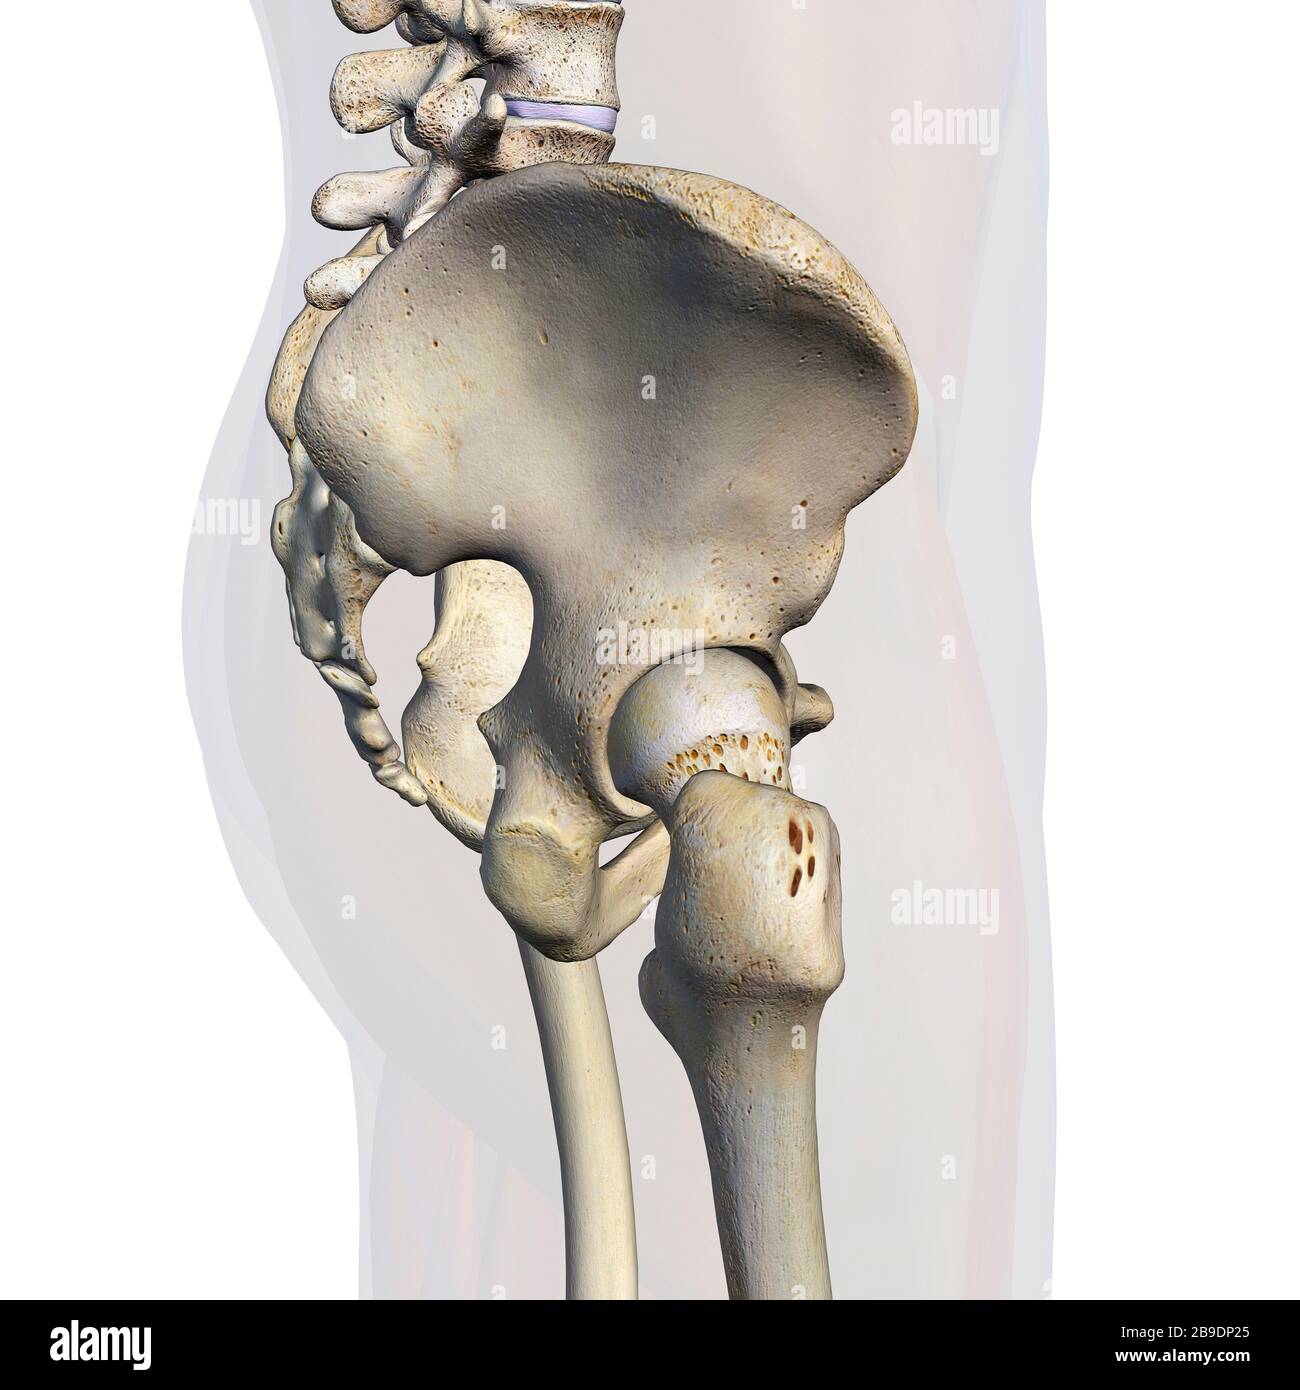

RFWW2CNW–Die männliche Anatomie, Gliedmaßen und hip Muskel- und Skeletterkrankungen Systeme, mit interner Muskelschichten. Vorder- und Rückansicht. schwarzen Hintergrund. 3d-Abbildung.

RFWW2BXR–Die männliche Anatomie, 3/4 Abbildung Muskel- und Skeletterkrankungen Systeme, Vorderansicht auf weißem Hintergrund. 3D-Anatomie Illustration.

RFWW2BT5–Die männliche Anatomie, 3/4 Abbildung Muskel- und Skeletterkrankungen Systeme, Rückansicht auf weißem Hintergrund. 3D-Anatomie Illustration.